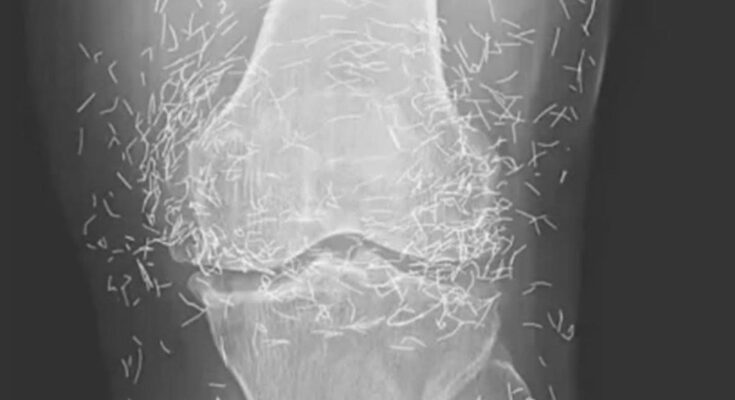

Acupuncture, an alternative treatment that has been around for centuries, involves the insertion of needles into specific points on the body to alleviate pain or address various health issues. In this particular case, the needles—likely made of gold—were deliberately left in her knees to provide ongoing stimulation.

He also cautioned that needles left embedded can interfere with X-ray interpretations. “The needles may obscure some of the anatomy,” Guermazi mentioned in 2013.

Even more alarming, leaving needles in the body can pose risks for future medical imaging. “The patient cannot undergo an MRI because the needles left inside may shift and harm an artery,” Guermazi noted.